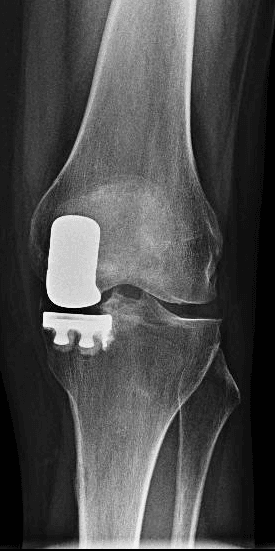

In caso di artrosi localizzata a un solo comparto del ginocchio, si preferisce l’uso di protesi monocompartimentali femoro-tibiali o femoro-rotulea, mantenendo intatte le componenti legamentose e le superfici cartilaginee non affette da artrosi.